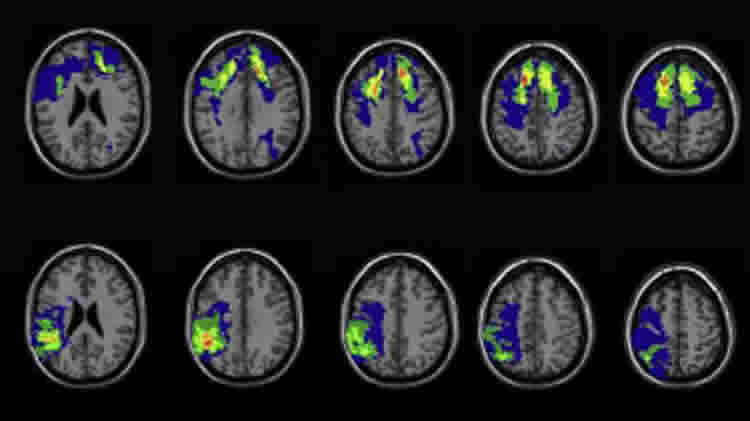

The researchers worked with test results from a group of veterans from the Vietnam War who had taken cognitive tests before and after the war. Using CT brain scan data, the researchers were able to examine how damage to certain parts of the brain affected the likelihood of having a mystical experience.

“Our study supports the ‘pull’ theory, as those who suffered traumatic injury to ‘God Spots’ were more likely to have mystical experiences,” says Dr Irene Cristofori from the Rehabilitation Institute of Chicago.

Image Credit: The image is credited to the researchers

Neural correlates of Mystical Experience

Mystical experiences, or subjectively believed encounters with a supernatural world, are widely reported across cultures and throughout human history. Previous theories speculate that executive brain functions underpin mystical experiences. To evaluate causal hypotheses, structural studies of brain lesion are required. Previous studies suffer from small samples or do not have valid measures of cognitive functioning prior to injury. We investigated mystical experience among participants from the Vietnam Head Injury Study and compared those who suffered penetrating traumatic brain injury (pTBI; n=116) with matched healthy controls (HC; n=32). Voxel-based lesion-symptom mapping analysis showed that lesions to frontal and temporal brain regions were linked with greater mystical experiences. Such regions included the dorsolateral prefrontal cortex (dlPFC) and middle/superior temporal cortex (TC). In a confirmatory analysis, we grouped pTBI patients by lesion location and compared mysticism experiences with the HC group. The dlPFC group presented markedly increased mysticism. Notably, longitudinal analysis of pre-injury data (correlating with general intelligence and executive performance) excludes explanations from individual differences. Our findings support previous speculation linking executive brain functions to mystical experiences, and reveal that executive functioning (dlPFC) causally contributes to the down-regulation of mystical experiences.